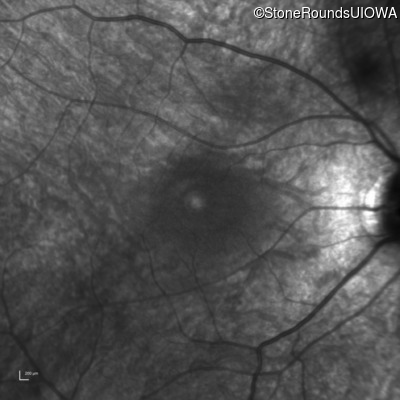

Infrared Fundus Photograph - Right - 20/100 -1

Exemplar